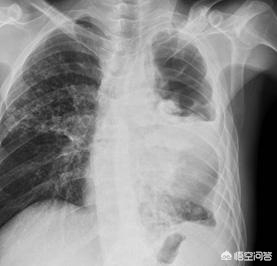

随着结核相关检查的不断问世,结核菌素试验的价值已经越来越低,试验阳性不能代表是结核病,试验阴性也不能完全排除结核感染,因为免疫力低下的人群明明感染结核这个试验也可能毫无反应而表现为阴性,结核感染最重要的还是胸部影像学检查和有创检查。